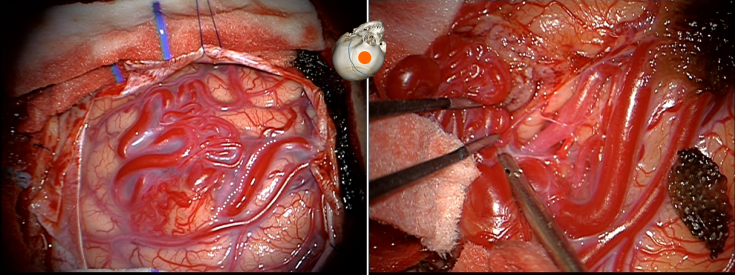

« go for the straights, beware of coils » (R Humphreys, Cf. schémat en frontispice et ci-dessous)

dans l’exemple ci-dessous, on identifie les pédicules artériels décochés par les branches sylviennes « en passant ». la corticotomie en arrière du nidus permet d’identifier les pédicules artériels (« straight« ) en respectant les veines artérialisées tortueuses (« coils« ). après dissection circonférentielle des artérioles, celles ci sont coagulées et sectionnées, en circonscrivant progressivement le nidus et en terminant par le ou les pédicules veineux.